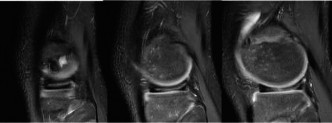

The correct answer is (B). The patient’s clinical examination is concerning for meniscal injury (lateral joint line pain) with the snapping sensation concerning for an unstable meniscus. The radiographs demonstrate lateral joint space widening, cupping of the lateral tibial plateau, and a hypoplastic lateral tibial spine—all suggestive of a discoid meniscus. Discoid menisci are classified using the Watanabe classification as complete, incomplete, or Wrisberg (lack of posterior meniscotibial attachment to the tibia). Unstable variants create the classic “snapping” sensation. The diagnosis of a discoid meniscus can be made with three or more 5-mm sagittal images with meniscal continuity. As the patient has had several months of pain with

mechanical symptoms and swelling, reassurance is not appropriate. Although IT band tendonitis can cause “snapping” it is not accompanied by loss of extension and swelling. Corticosteroid injections should be utilized sparingly in the pediatric population; particularly when a diagnosis has not been made. The patient then obtains an MRI which is shown inFigure 10–30. The next appropriate step in management is:

Figure 10–30